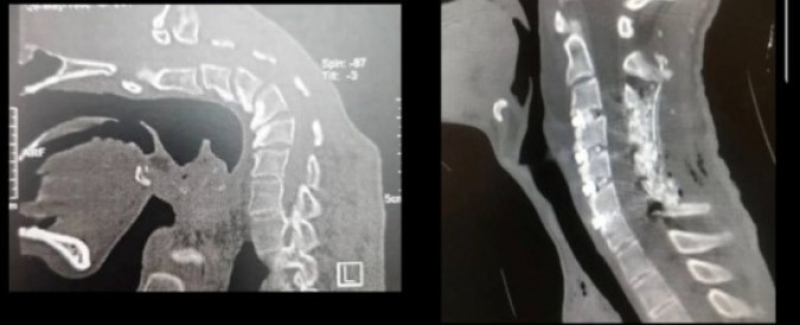

เมื่อเวลาผ่านไป กระดูกสันหลังส่วนคอของเขาเริ่มผิดรูป โดยเฉพาะบริเวณข้อ C3–C5 จนศีรษะของเขาก้มลงเกือบ 90 องศาแตะหน้าอก และไม่สามารถยกศีรษะขึ้นเองได้ ซึ่งเป็นลักษณะของ “โรคหัวตก” ที่มักเกิดจากภาวะกล้ามเนื้อคอลีบหรือความผิดปกติของระบบประสาท จากการตรวจร่างกายและระบบประสาทของผู้ป่วย ทีมแพทย์ยืนยันว่าไม่พบความผิดปกติในเส้นประสาทหรือโรคกล้ามเนื้ออื่นๆ ที่มักเป็นสาเหตุของภาวะนี้ ทำให้แพทย์สรุปว่าสาเหตุหลักของโรคหัวตกในกรณีนี้คือ “พฤติกรรมก้มศีรษะซ้ำๆ เป็นเวลานานหลังใช้ยาเสพติด” ซึ่งไม่เคยมีรายงานมาก่อนในวงการแพทย์

แพทย์ได้ทำการผ่าตัดกระดูกสันหลังส่วนคอด้วยวิธี 3 ขั้นตอน โดยการตัดแต่งกระดูกและกล้ามเนื้อบางส่วน แล้วใช้โลหะช่วยยึดเพื่อปรับแนวกระดูกให้กลับมาตรง ผลการผ่าตัดประสบความสำเร็จ ผู้ป่วยสามารถลุกขึ้นและเดินได้ในวันถัดมา และออกจากโรงพยาบาลภายใน 3 วัน และหลังติดตามอาการเป็นเวลา 1 ปี พบว่าแนวกระดูกคอดีขึ้นอย่างเห็นได้ชัด และผู้ป่วยสามารถเลิกยาเสพติดได้สำเร็จ